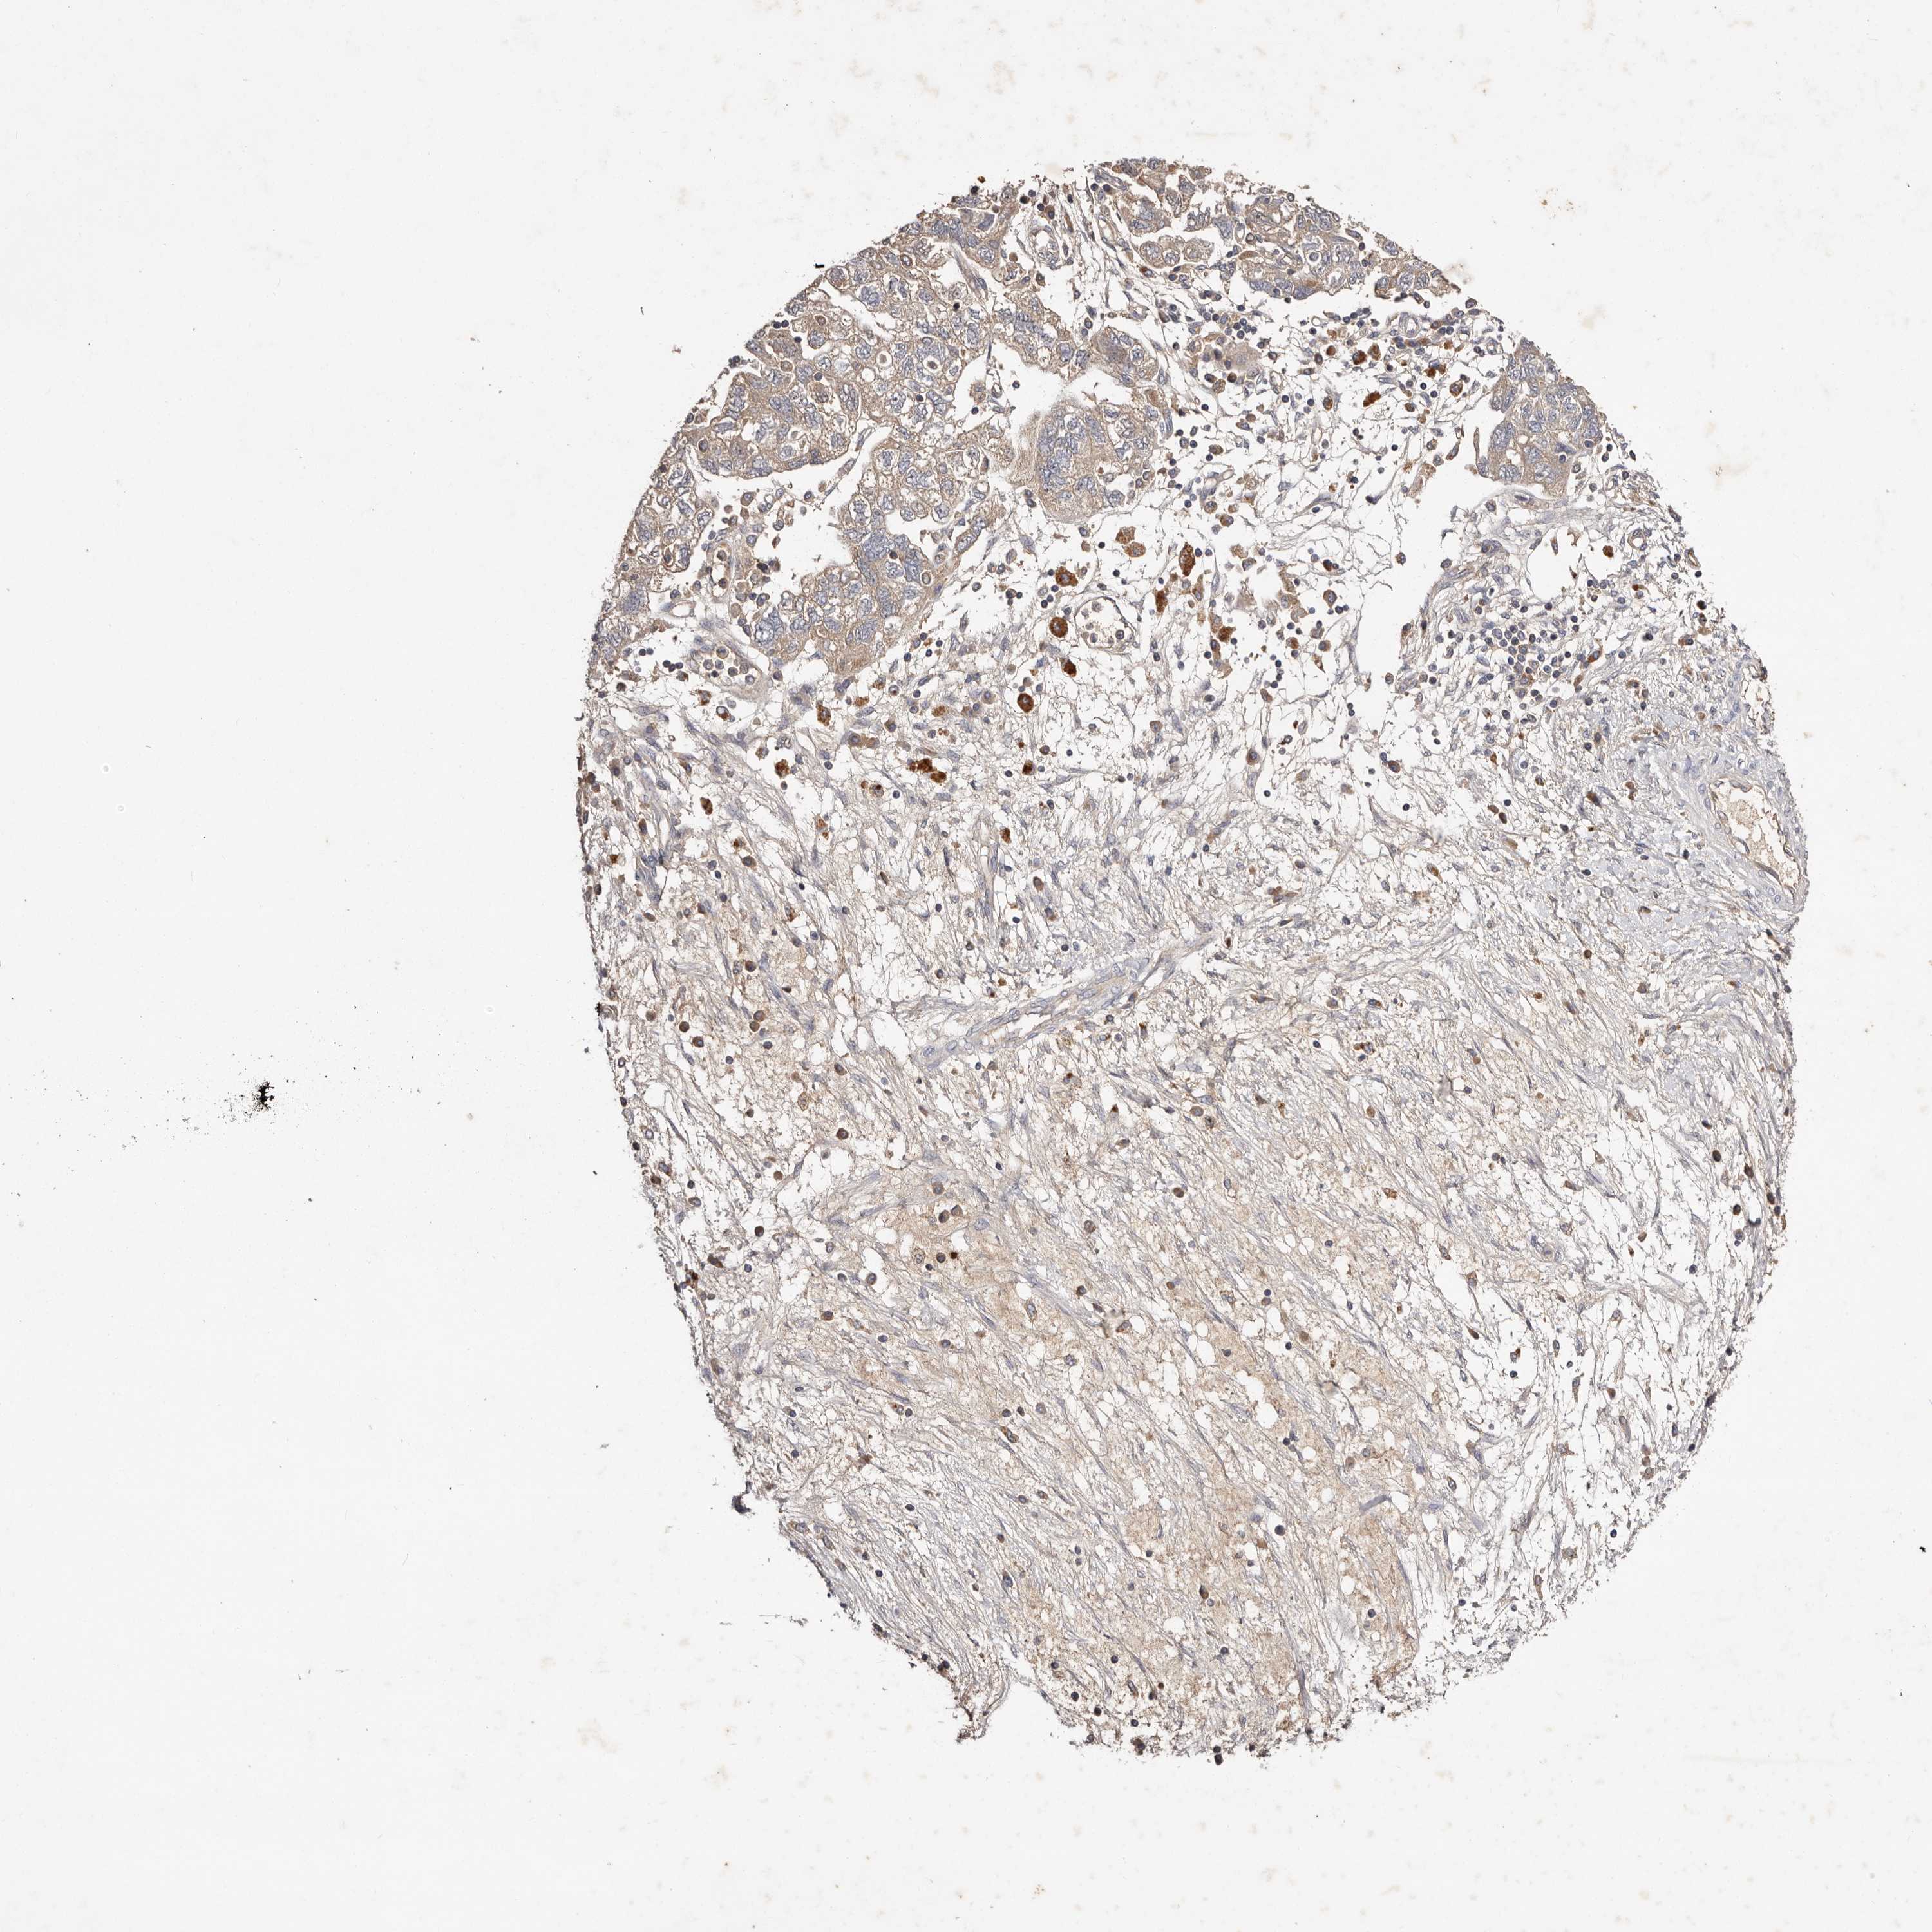

OVARIAN CANCER - Protein expressioni

A mouse-over function shows sample information and annotation data. Click on an image to view it in a full screen mode. Samples can be filtered based on level of antibody staining by selecting one or several of the following categories: high, medium, low and not detected. The assay and annotation is described here.

Note that samples used for immunohistochemistry by the Human Protein Atlas do not correspond to samples in the TCGA dataset.

Antibody stainingi

Antibody staining in the annotated cell types in the current human tissue is reported as not detected, low, medium, or high, based on conventional immunohistochemistry profiling in selected tissues. This score is based on the combination of the staining intensity and fraction of stained cells.

Each image is clickable and will lead to virtual microscopy that enables deeper exploration of all samples and also displays staining intensity scores, fraction scores and subcellular localization as well as patient and tissue information for each sample.

Antibody HPA030159

Antibody HPA030160

Antibody HPA030161

Carcinoma, endometroid